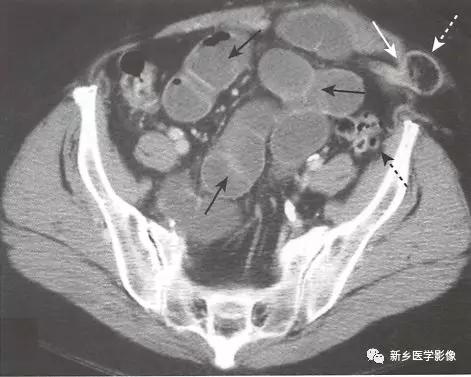

4、小肠梗阻的CT表现如下

梗阻近端可见小肠肠襻扩张且腔内充满液体(直径>2.5cm )。

识别移行点,即肠道管径由扩张到正常的地方,提示梗阻部位。 如果在移行点未看到明确肿块或其他梗阻原因,则几乎可以肯定为粘连所致。

梗阻远端的小肠或结肠肠腔塌陷。

小肠粪便征。 小肠梗阻移行点近端的肠道内聚集肠道碎片和液体,形成类似粪便的外观,是小肠梗阻的征象。

闭襻性肠梗阻指同一肠襻的两个点在同一位置发生梗阻,闭襻通常形成U形或C形的扩张肠襻。 大多数的闭襻性肠梗阻由粘连所致。 小肠的闭襻性肠梗阻发生肠绞窄的风险更高。 大肠的闭襻性肠梗阻被称为肠扭转。

绞窄。 肠缺血可通过增强CT中肠壁环形增厚且肠壁强化减低来诊断,通常合并肠系膜水肿及腹腔积液。